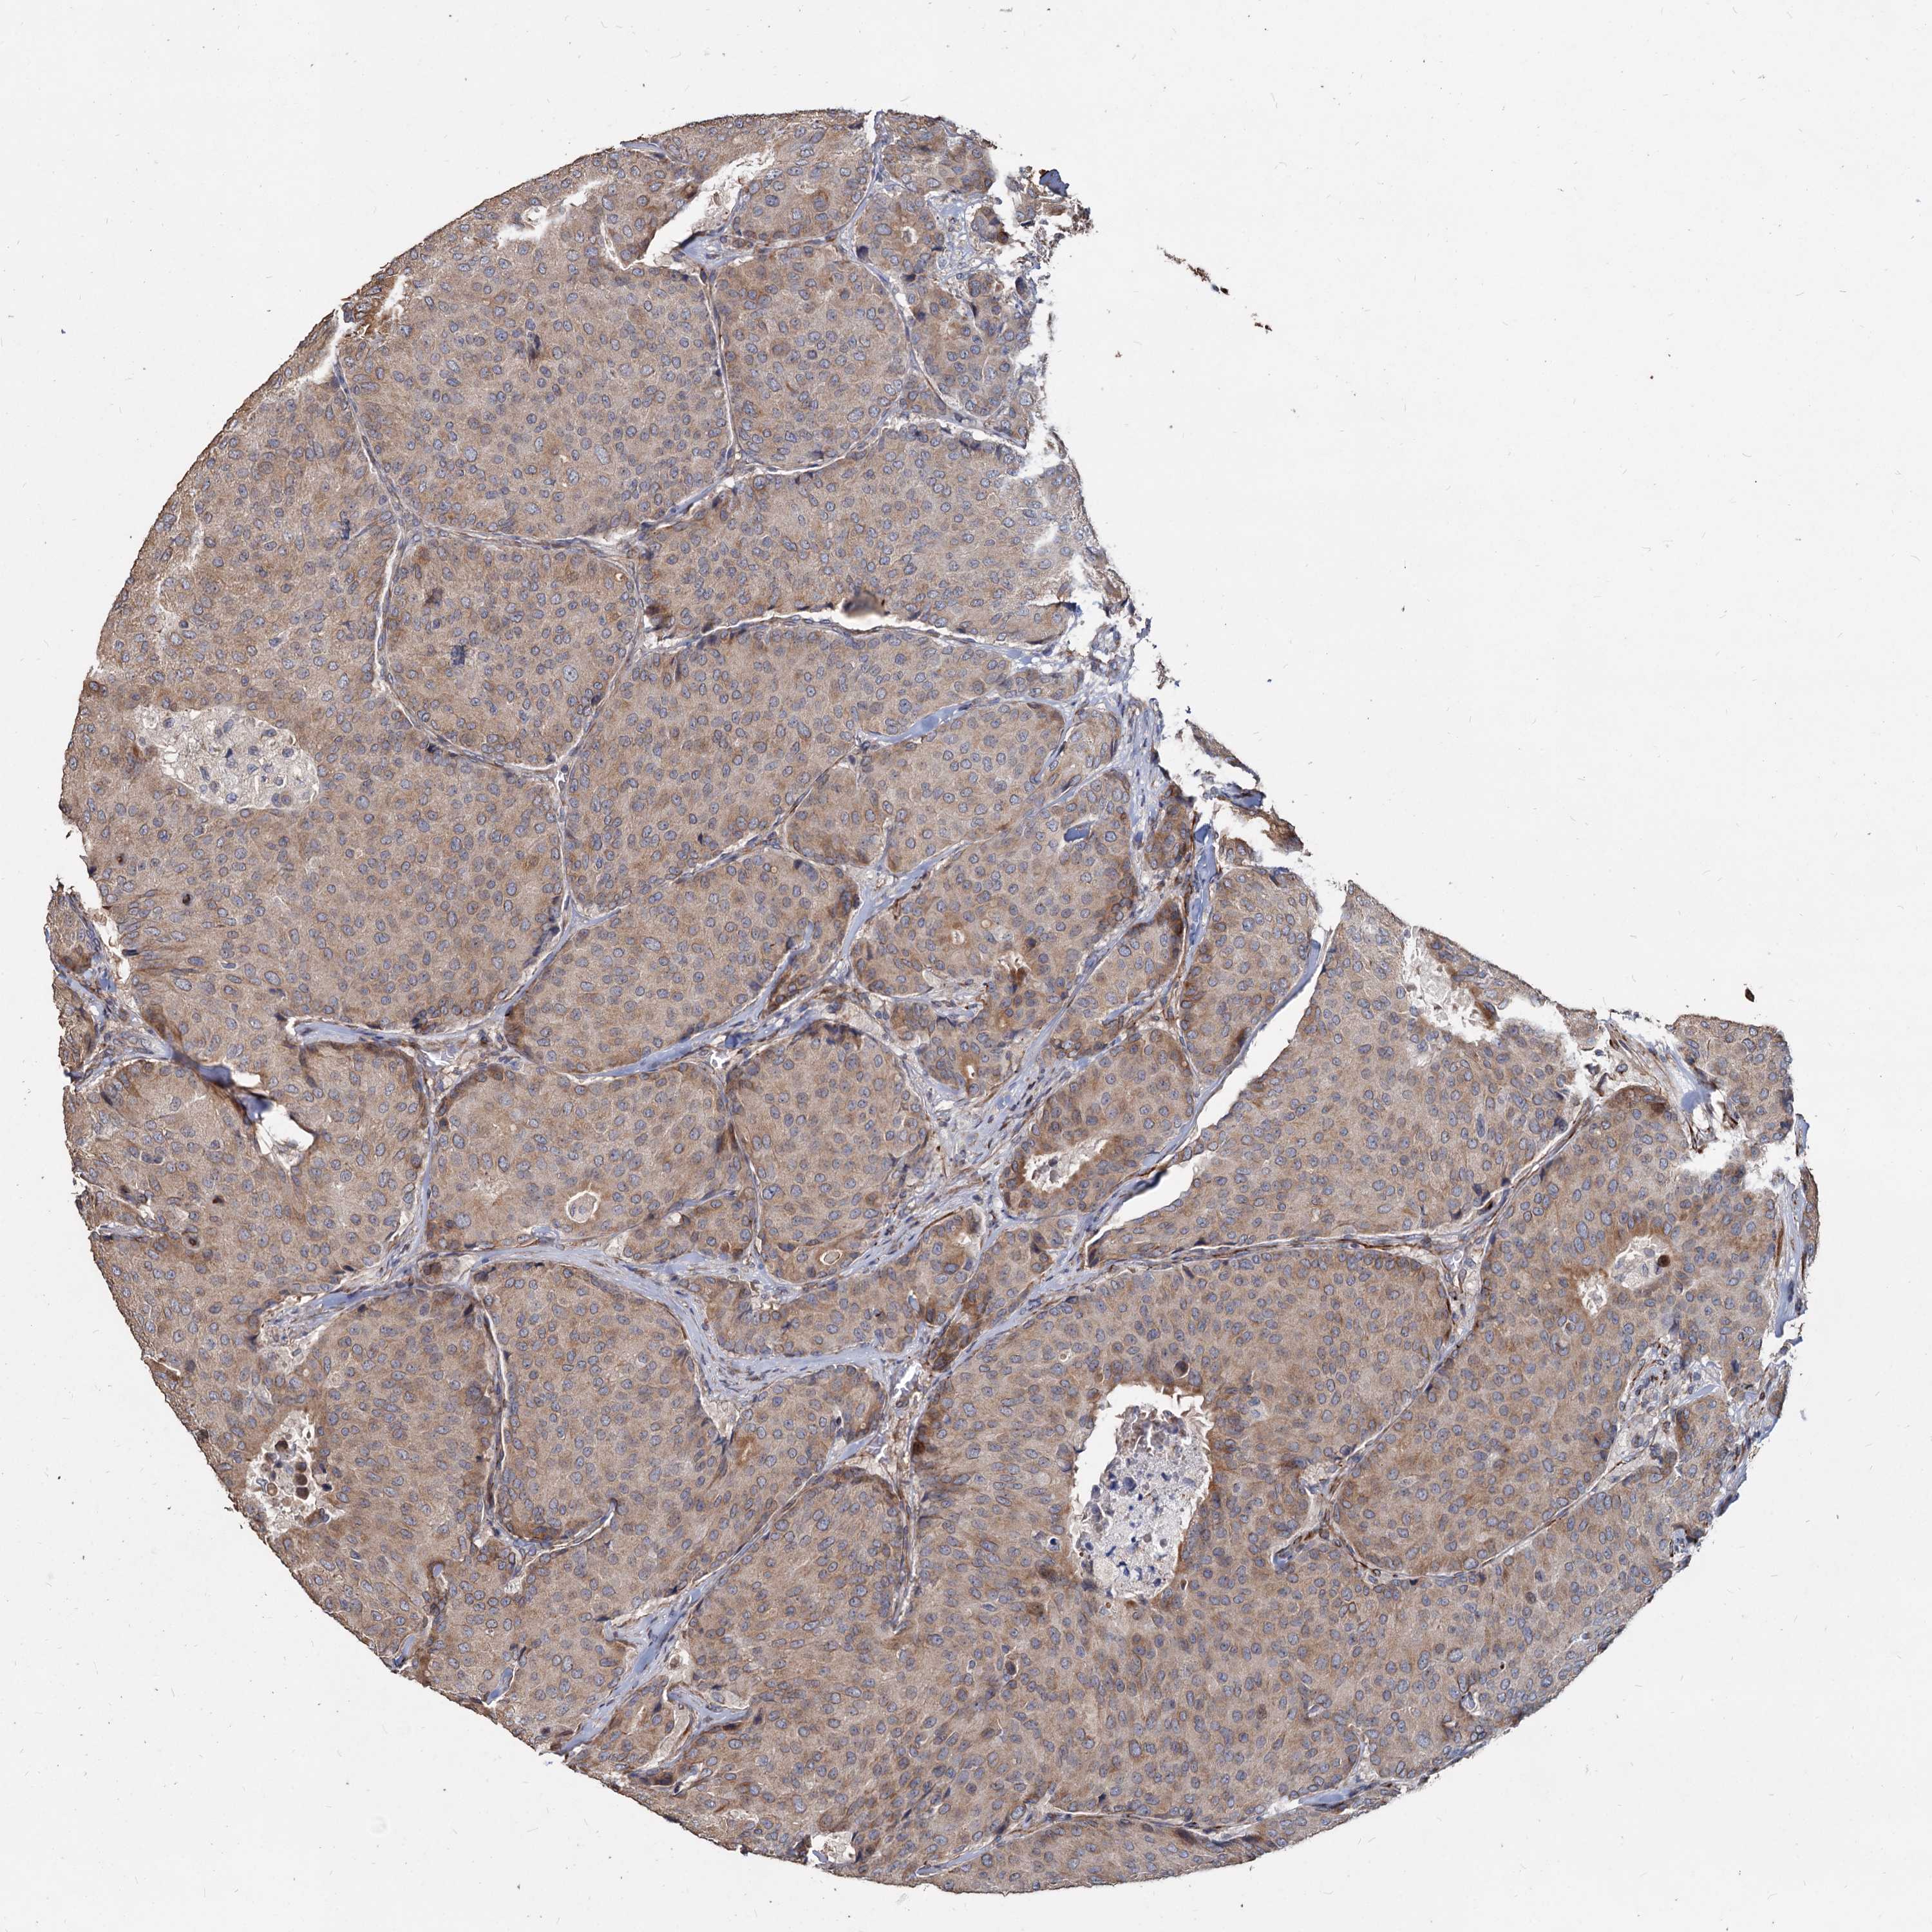

CANCER BREAST CANCER Show tissue menu

BRCA TCGA BRCA VALIDATION PROTEIN EXPRESSION